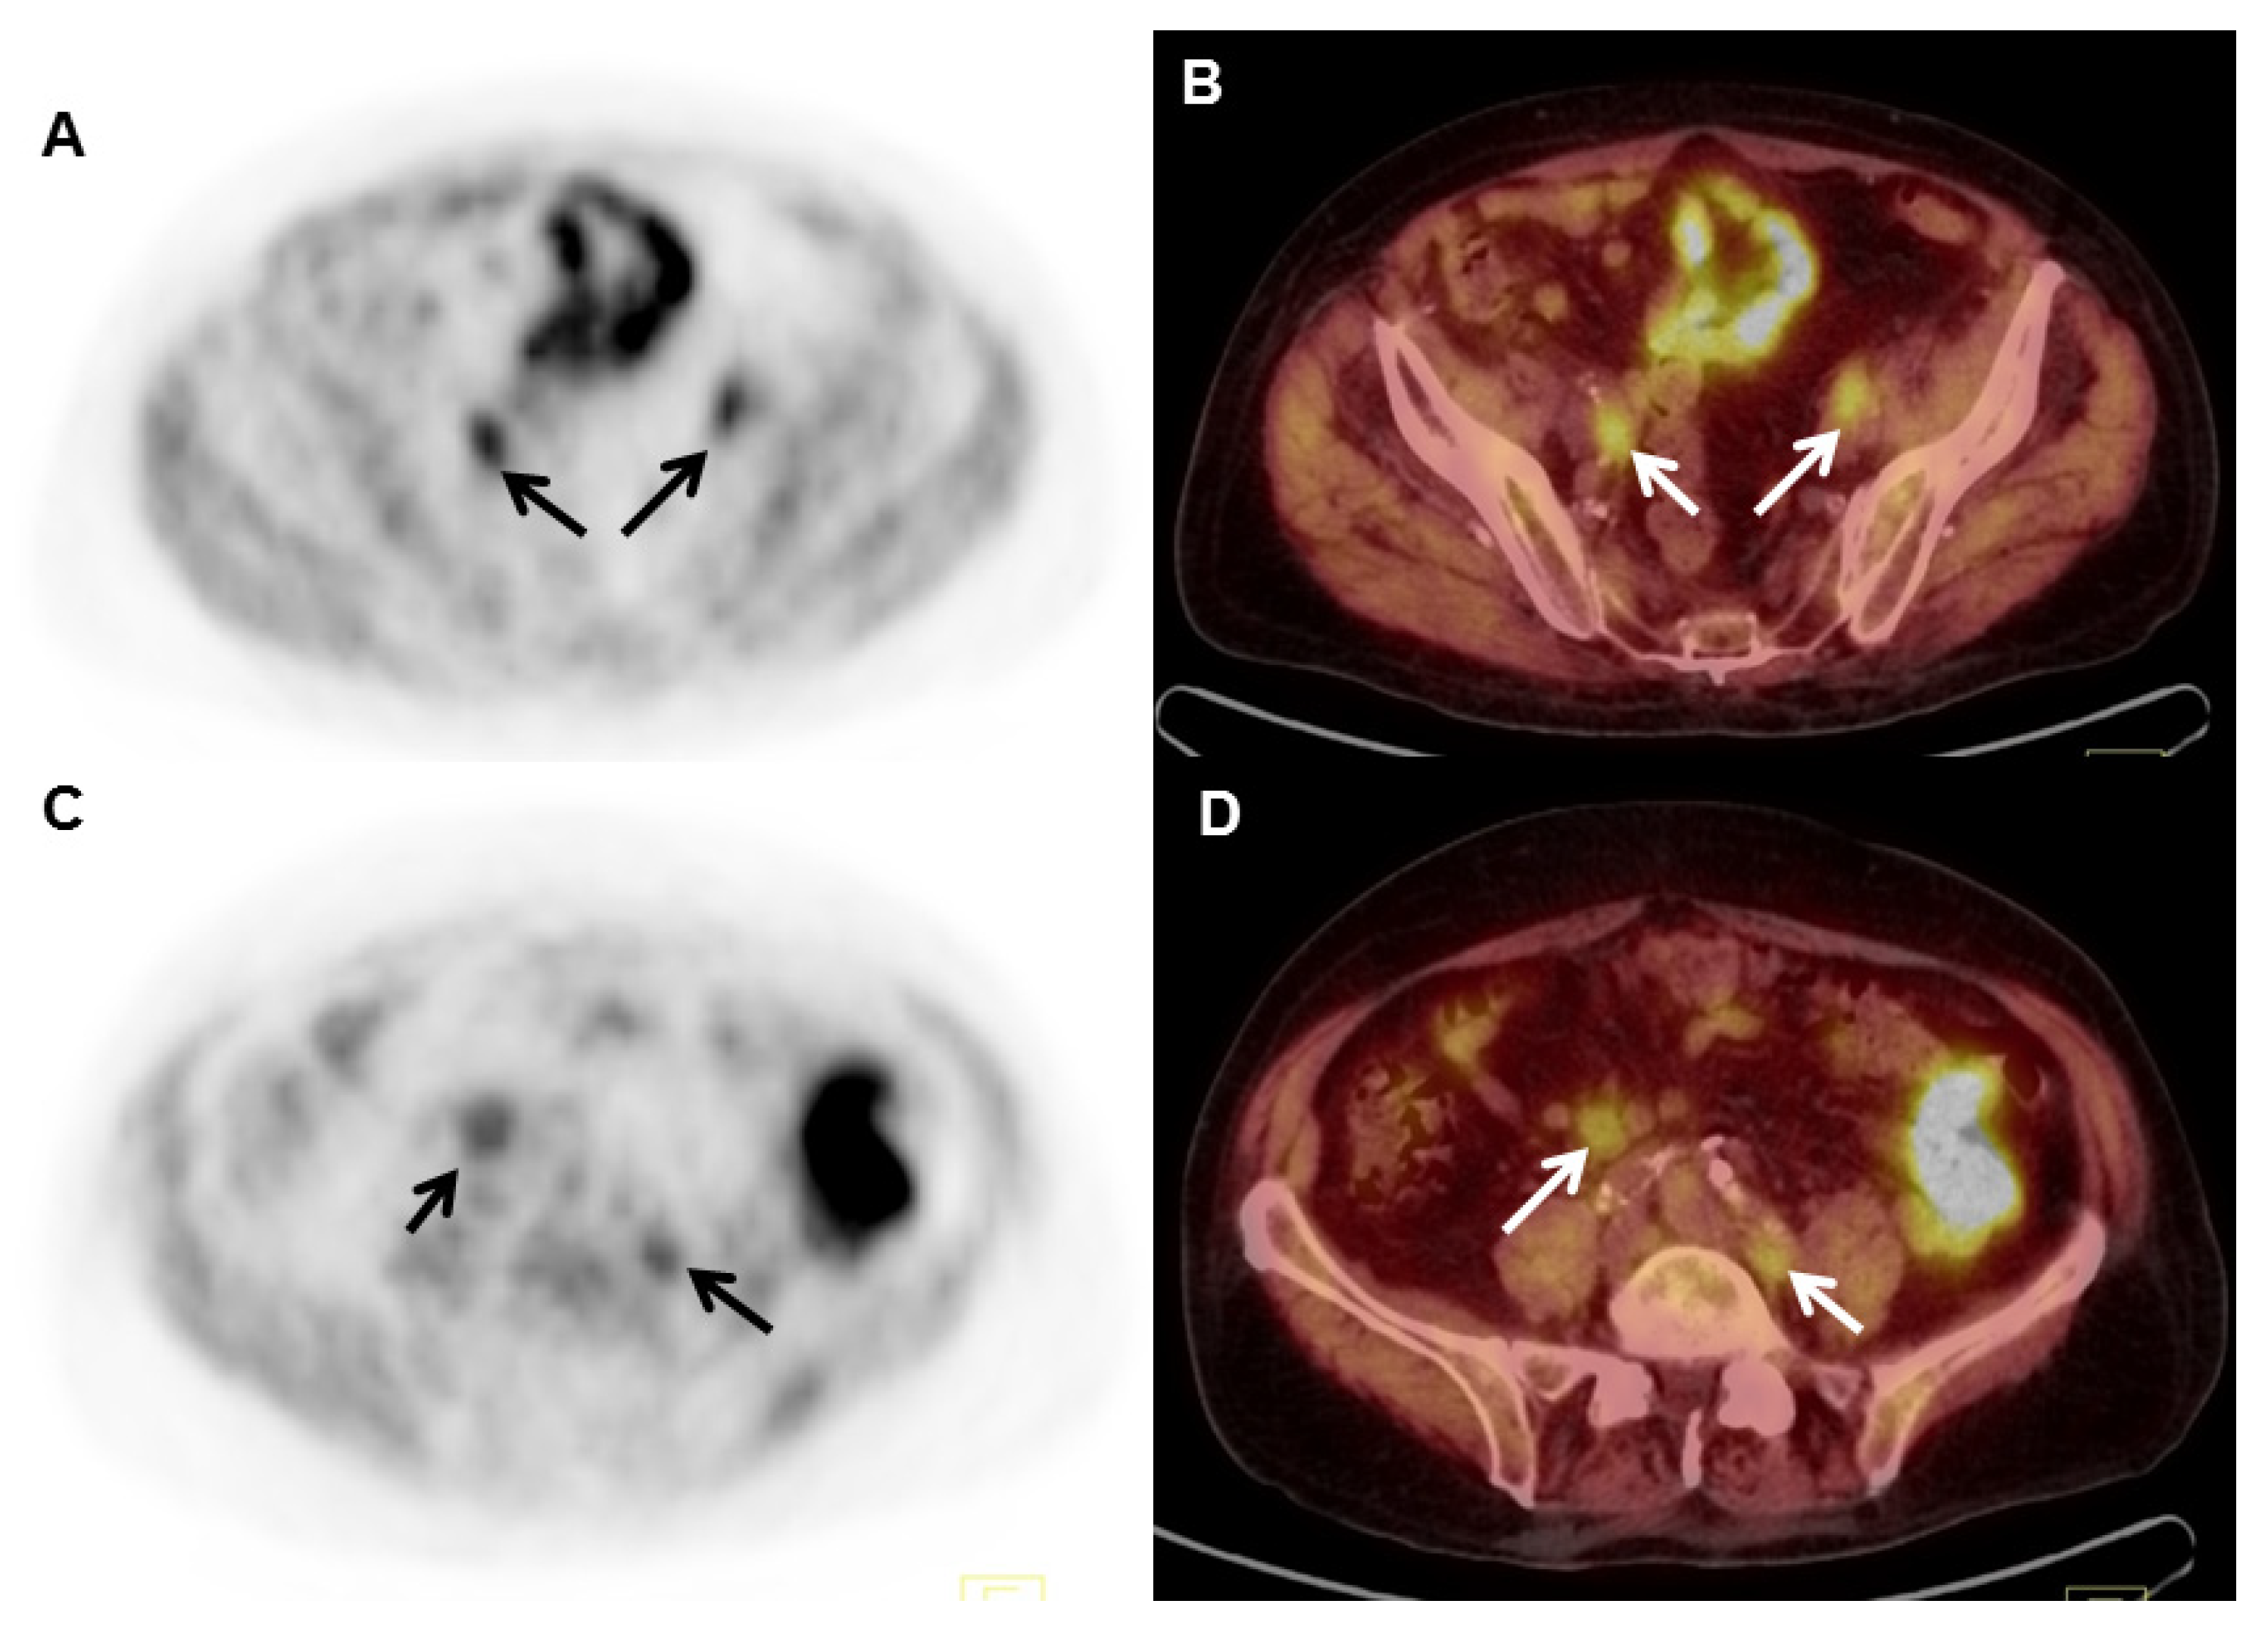

2.4. 18F-Fluciclovine (FACBC) PET